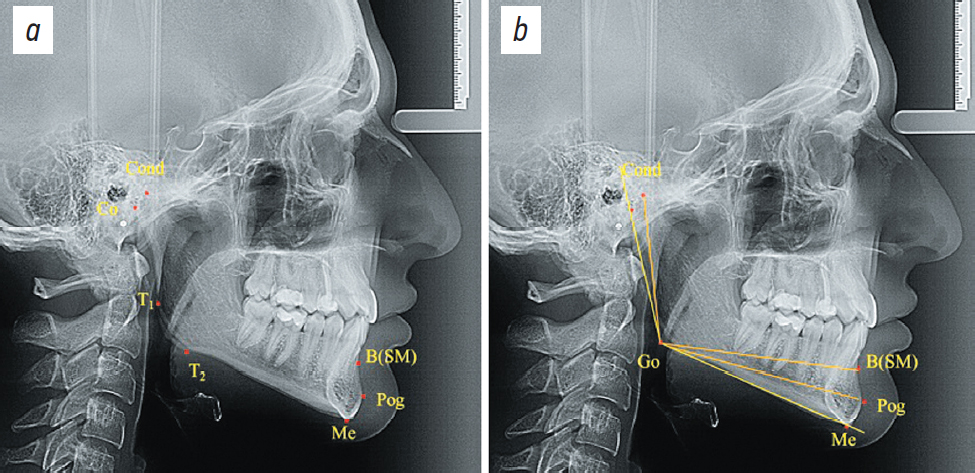

Для людей со средними размерами подбородка разница между размерами длины альвеолярной части и расстоянием Gо-Pog составила от 2,1 до 4,8 мм. Увеличение разницы в размерах более чем на 4,9 мм была характерна для людей с длинным подбородком, менее 2 мм — с коротким подбородком (рис. 2).

Рис. 2. Положение точечных и линейных ориентиров при средних (а) длинных (b) и коротких (c) размерах подбородка.

Fig. 2. Location landmarks and linear measurements for chins of average (a), long (b) and short (c) dimensions.

При анализе телерентгенограмм людей со средними размерами подбородочного выступа (1-я группа) установлено, что высота ветви нижней челюсти (Gо-Сond) в среднем по группе людей с разными вариантами физиологического прикуса составляла 58,04±0,43 мм. При длине тела нижней челюсти (Gо-Ме) 72,37±1,19 мм соотношение тела к ветви составило 1,25±0,03. Длина альвеолярной части нижней челюсти Gо-B(SM) составила 74,02±1,06 мм, ее отношение к высоте ветви — 1,28±0,02. Разница между длинной альвеолярной части и расстоянием Gо-Pog (76,32±0,76 мм) составила 3,36±0,56 мм, что определило среднюю длину подбородочного выступа. Разница в показателях, полученных у всех обследованных 1-й группы, была недостоверной (р >0,5).

При анализе телерентгенограмм 2-й группы, с относительно длинными размерами подбородочного выступа, установлено, что высота ветви нижней челюсти (Gо-Сond) в среднем по группе людей с разными вариантами физиологического прикуса составляла 57,26±0,86 мм. При длине тела нижней челюсти (Gо-Ме) 72,29±0,82 мм соотношение тела к ветви составило 1,27±0,02. Длина альвеолярной части нижней челюсти Gо-B(SM) составила 71,27±1,02 мм, а ее отношение к высоте ветви — 1,25±0,02.

Разница между длиной альвеолярной части и расстоянием Gо-Pog (77,74±0,87 мм) составила 6,47±0,51 мм, что соответствовало длинным размерам подбородочного выступа; разница в показателях, полученных у людей со средними размерами подбородка, была достоверной (р <0,5).

На телерентгенограммах 3-й группы, с относительно короткими размерами подбородочного выступа, установлено, что высота ветви нижней челюсти (Gо-Сond) в среднем по группе, составляла 59,42±1,22 мм. При длине тела нижней челюсти (Gо-Ме) 67,24±1,18 мм соотношение тела к ветви составило 1,13±0,04. Длина альвеолярной части нижней челюсти Gо-B(SM) составила 72,85±1,27 мм, а ее отношение к высоте ветви — 1,23±0,02.

Разница между длинной альвеолярной части и расстоянием Gо-Pog (73,74±0,91 мм) составила 0,88±0,62 мм, что соответствовало коротким размерам подбородочного выступа, разница в показателях, полученных у людей со средними размерами подбородка, была достоверной (р <0,5).